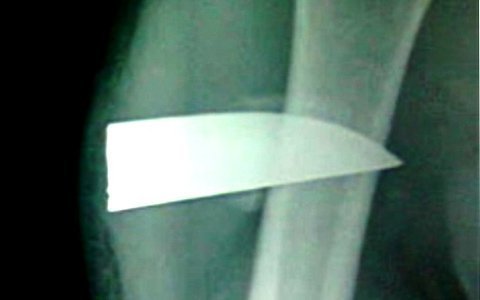

Ngày 29/10, tin từ Bệnh viện Hữu nghị Việt Nam - Cu Ba Đồng Hới (Quảng Bình),

cho biết các bác sĩ tại đây đã thực hiện ca phẫu thuật thành công và rút được

lưỡi dao dài khoảng 7cm, cắm sâu trong cánh tay của một nam thanh niên cách

đây hơn 4 tháng.

| Mũi dao dài 7cm đâm sâu, nhưng may mắn Nam không bị liệt tay vì được xương định vị (hình chụp X-quang của bệnh viện). |

Bệnh nhân nói trên là Trần Bắc Nam (22 tuổi), trú tại xã Xuân Trạch, huyện Bố

Trạch (Quảng Bình). Điều may mắn là vì đã cắm sâu vào xương nên mũi dao bị định

vị một chỗ. Nếu không, Nam rất dễ bị liệt tay bởi mũi dao di chuyển và cắt đứt

các tổ chức xung quanh như dây thần kinh, cơ, mạch máu…